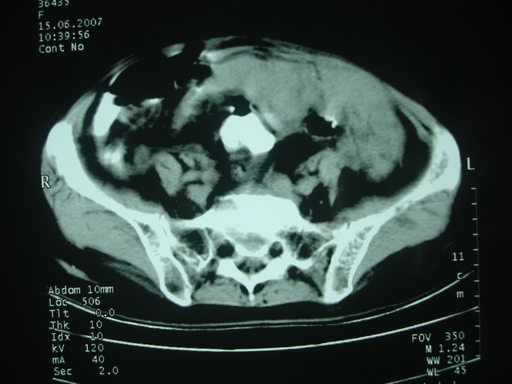

女,70岁,自述锻炼时牵拉导致左下腹疼痛,后疼痛加剧,发现包块10天,家属说其他检查,无法热,大便正常,一般情况差,痛苦面容,左下腹压痛明显,口服造影剂后腹泻,钡灌肠降结肠迂曲粘膜未见异常。抗炎治疗一周后诉症状减轻。

以下图考虑是何病?谢谢!

大网膜血肿?建议增强进一步检查。

支持大网膜血肿

盆腔附件区不规则软组织密度影,与下腹部异常密度影相联,建议进一步检查除外妇科疾患!